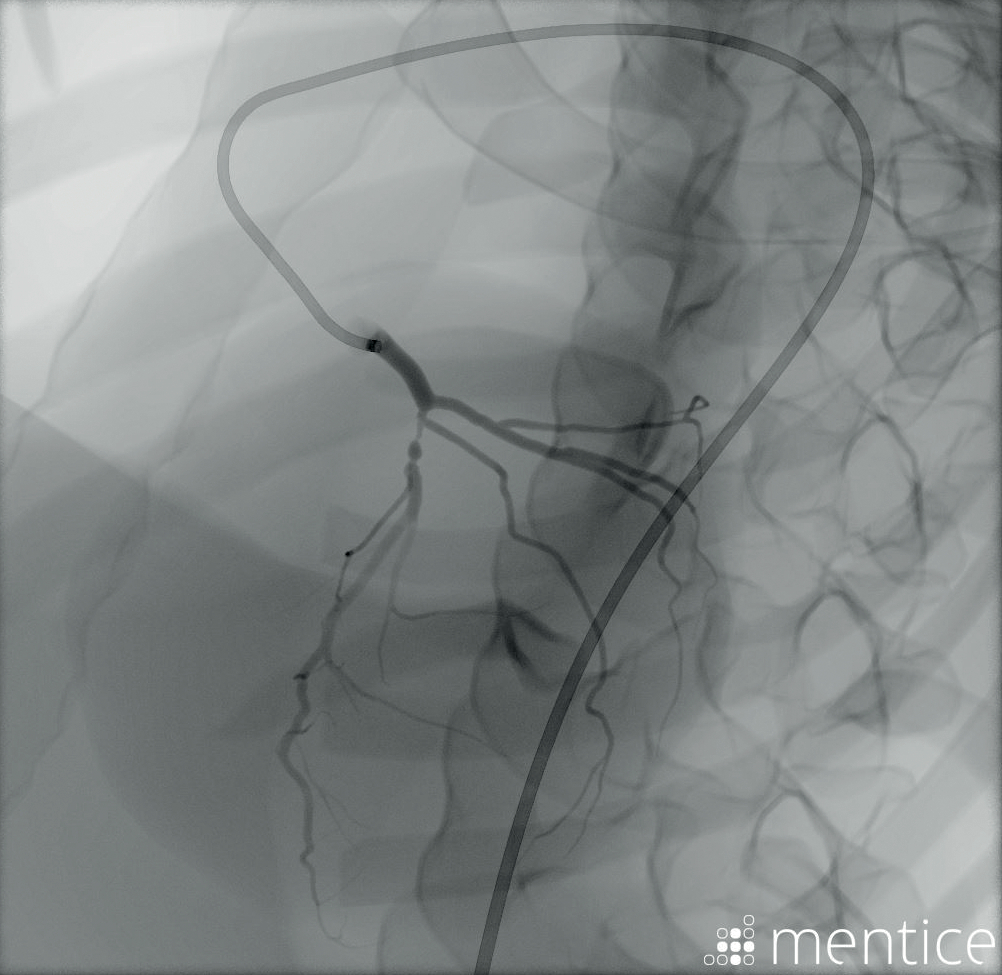

Start-to-end simulation

从公关遵循SimMan血管随着训练e-hospital to in-hospital recovery environment. Optimize the patient pathway and perform continuous improvements for critical care patients.

SimMan Vascular allows hospitals to improve processes and update protocols, providing the opportunity to practice basic and advanced clinical skills without risk to patients.